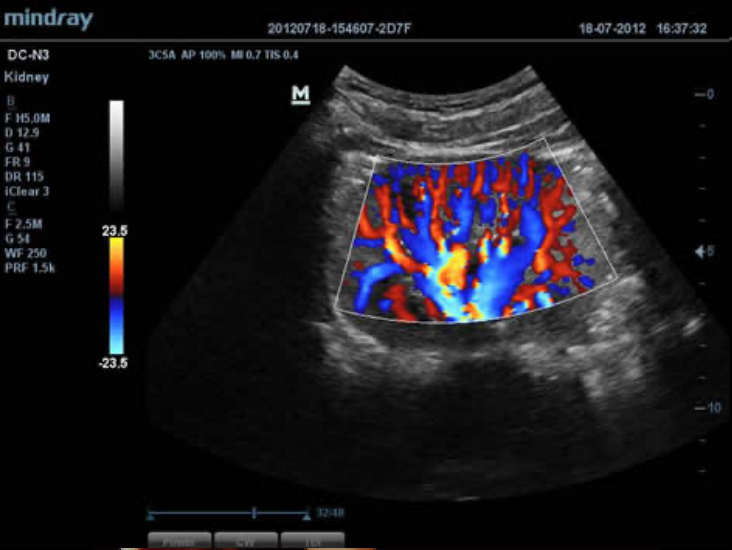

El DC-N3 PRO es la respuesta a sus requisitos de alta calidad de la imagen, versatilidad y asequibilidad. El DC-N3?PRO es el mejor equipo en su clase y es realmente una redefiniciĂłn de los principios bĂĄsicos que le brinda mucho mĂĄs que tan solo un sistema ecogrĂĄfico normal. Con caracterĂsticas avanzadas y el precio mĂĄs competitivo de la industria, se trata de ayudarlo a elevar sus expectativas.

El DC-N3 PRO es un sistema Doppler a color con todas las funciones que satisface sus necesidades de diagnĂłsticos mĂĄs rĂĄpidos, confiables y precisos. Gracias al mejor rendimiento, eficacia y dise?o de su clase, puede estar seguro de que obtendrĂĄ una experiencia de ecografĂa excepcional. Con su dise?o compacto, fĂĄcil de usar y ergonĂłmico, se puede mover, usar y ubicar segĂșn sus requisitos sin lĂmites.